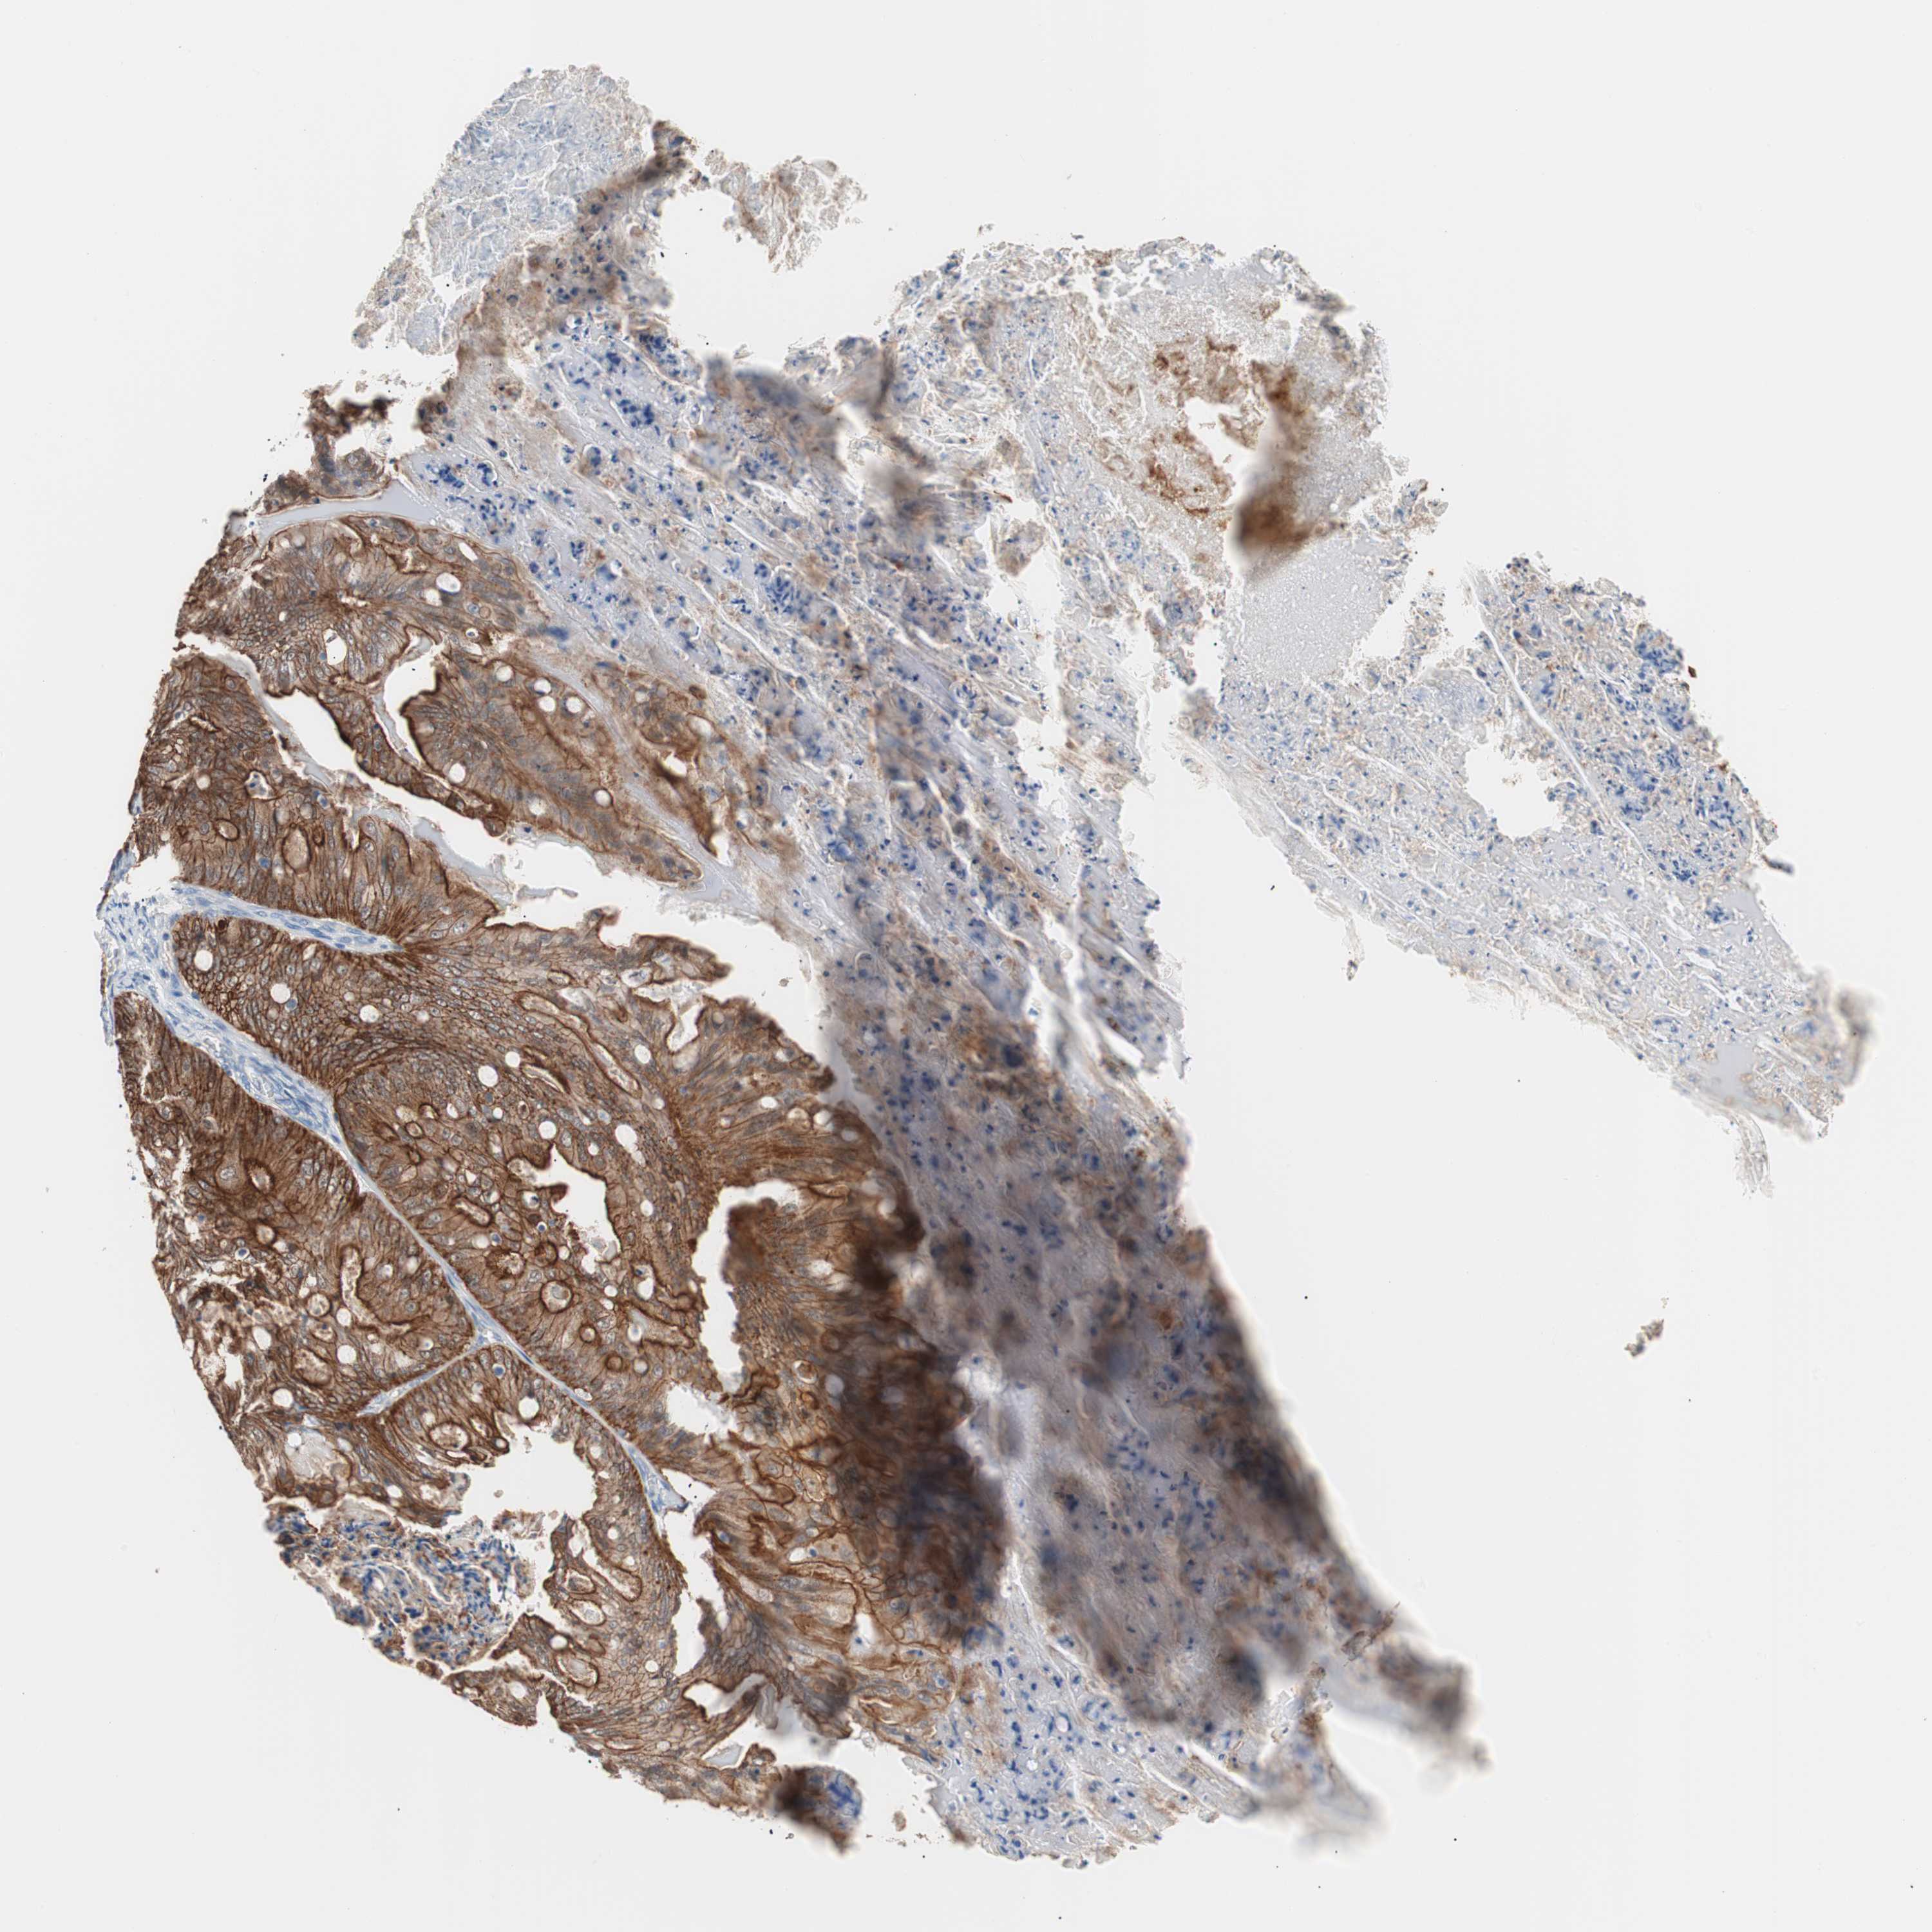

OVARIAN CANCER - Protein expressioni

A mouse-over function shows sample information and annotation data. Click on an image to view it in a full screen mode. Samples can be filtered based on level of antibody staining by selecting one or several of the following categories: high, medium, low and not detected. The assay and annotation is described here.

Note that samples used for immunohistochemistry by the Human Protein Atlas do not correspond to samples in the TCGA dataset.

Antibody stainingi

Antibody staining in the annotated cell types in the current human tissue is reported as not detected, low, medium, or high, based on conventional immunohistochemistry profiling in selected tissues. This score is based on the combination of the staining intensity and fraction of stained cells.

Each image is clickable and will lead to virtual microscopy that enables deeper exploration of all samples and also displays staining intensity scores, fraction scores and subcellular localization as well as patient and tissue information for each sample.

Antibody HPA006884

Antibody HPA006885

Antibody CAB002452

Cystadenocarcinoma, serous, NOS

Carcinoma, endometroid

Carcinoma, NOS

Cystadenocarcinoma, mucinous, NOS